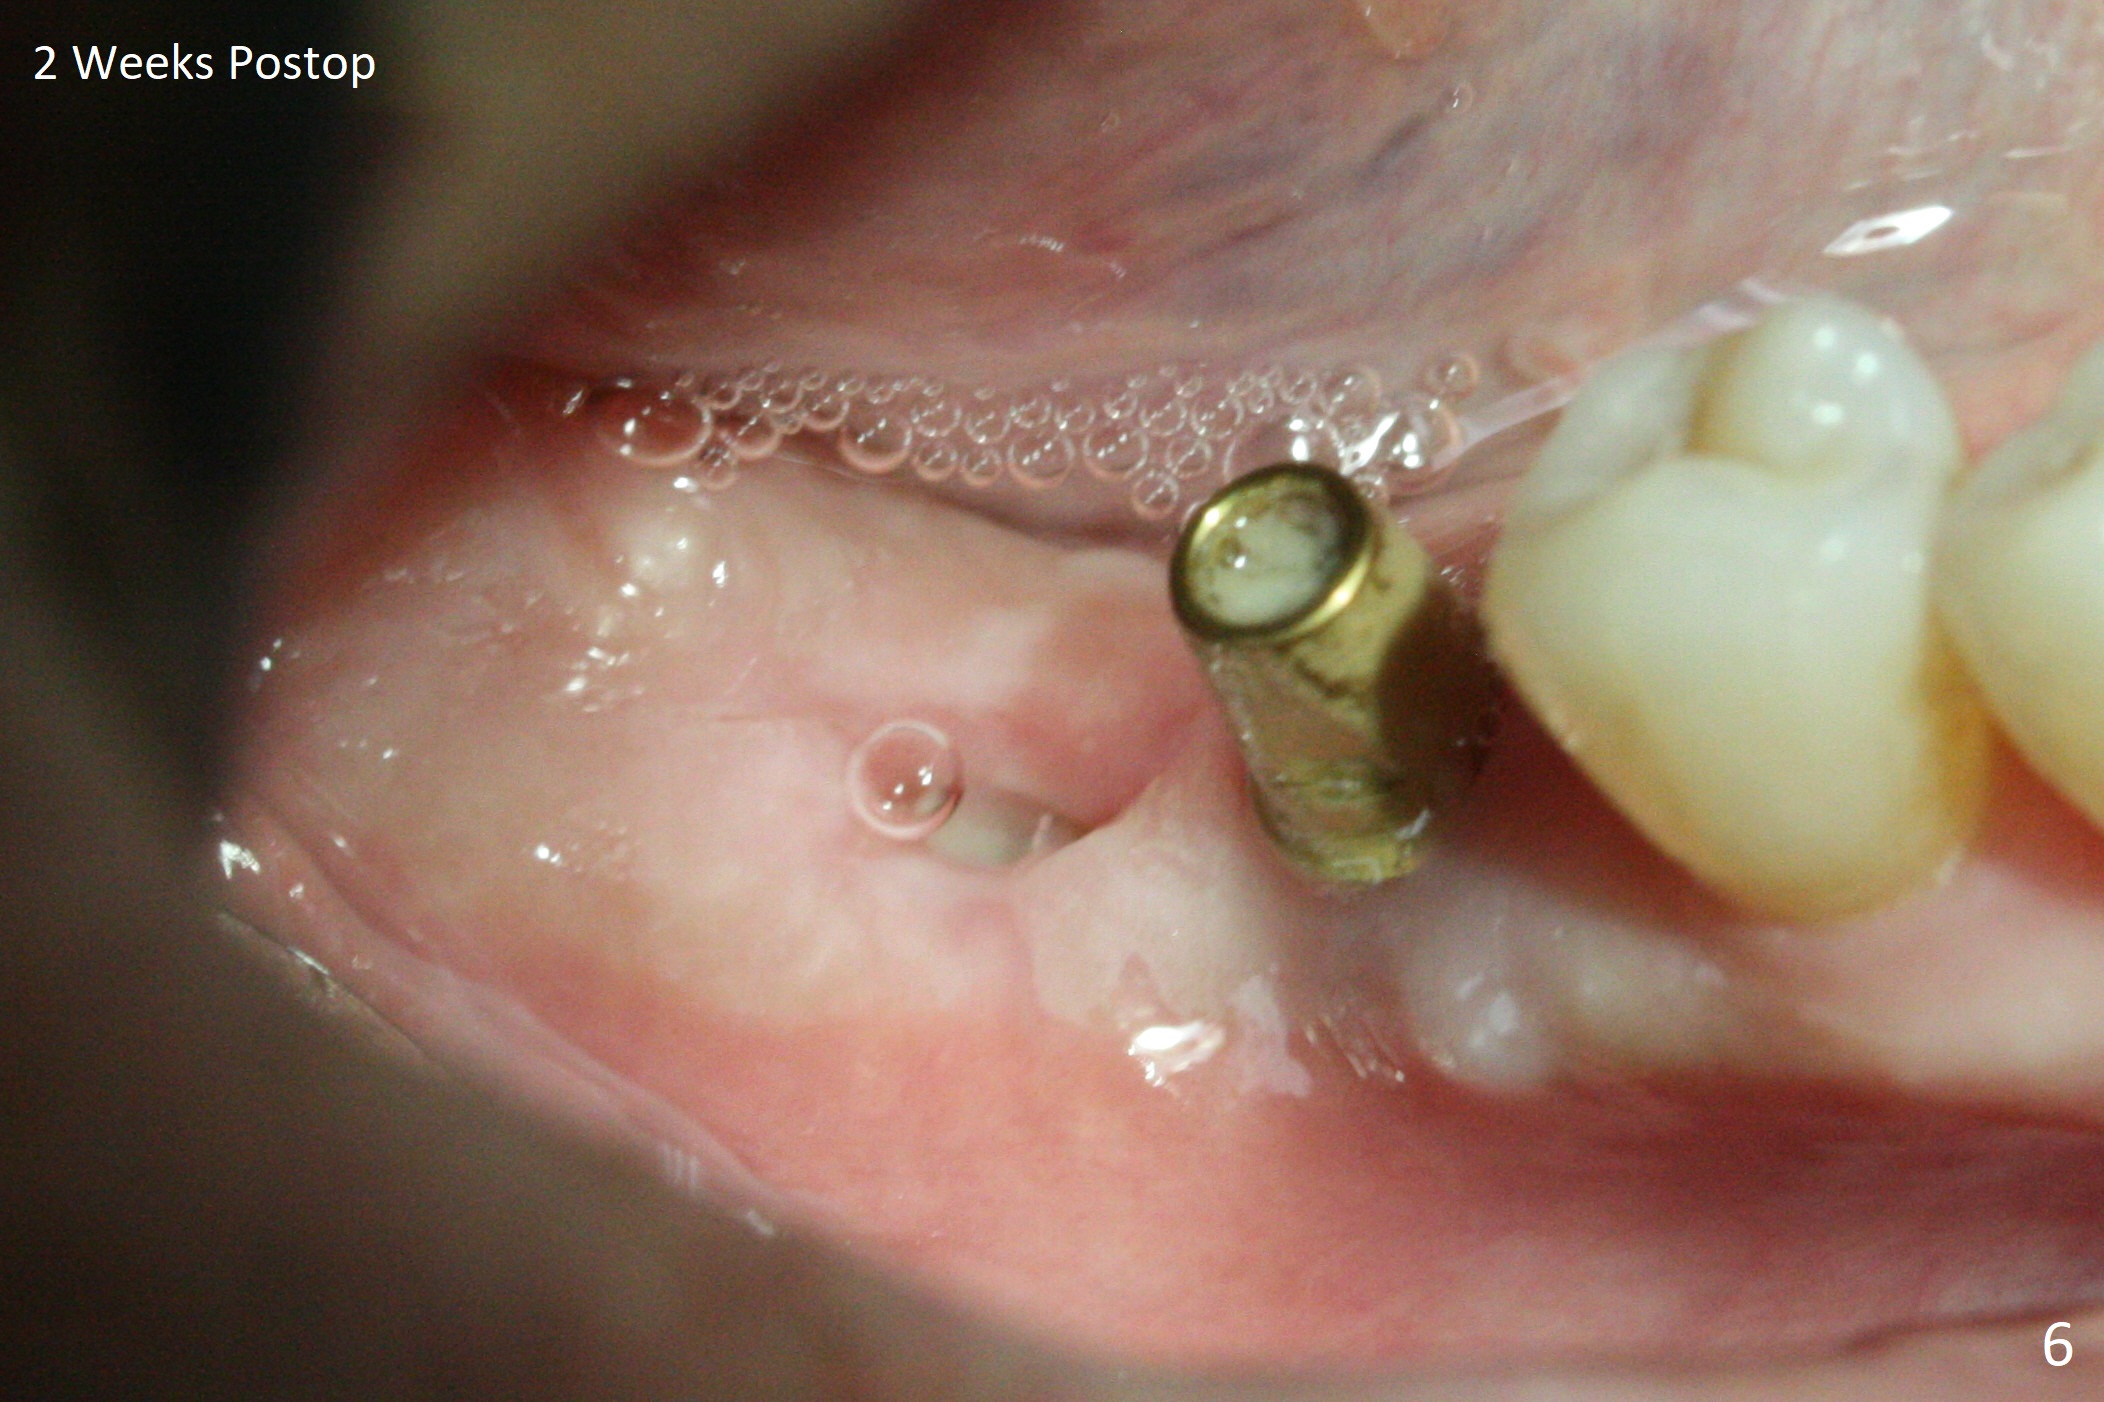

Osteotomy at the sites of #30 and 31 is initiated with Magic Split, followed by Magic Expanders (3.0 and 3.8 mm) at #31. Initial depth of osteotomy is 13 mm with 2.2 mm drill (Fig.1). After adjustment of the trajectory at #31 (Fig.1 arrow) and deepening the osteotomy by 2 mm, dummy implants are placed with stability (Fig.2). Following increase in osteotomy at #31, the larger implant in fact loses stability (Fig.3). The loose implant is pushed distal (Fig.4 arrow) with placement of autogenous bone mesial (*). The stable implant at #30 (Fig.3) and its abutment (Fig.4) are used as a post to hold periodontal dressing, which covers the wound at #31 after placement of collagen plug and suturing. In fact the same technique could be used when socket preservation was performed if an implant were placed at #30 at the same time. When the periodontal dressing dislodges, the wound at #31 heals uneventfully (Fig.5,6). The bone graft seems to remain in place 3 months postop (Fig.7). The implant is uncovered with placement of a 6.8x7 mm healing abutment 4 months postop. When a cementation abutment is placed and prepped, the buccal margin is much lower than the lingual (Fig.8 taken prior to cementation). The patient enjoys mastication with the new implant crowns 3.5 months post cementation (Fig.9).